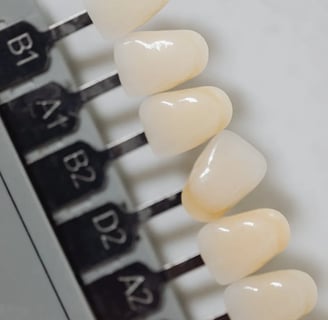

Stomatologie estetica

Albire dentară cu laser, fațete dentare și restaurări cosmetice pentru un zâmbet radiant.

Protetică dentară:

Refacerea dinților lipsă sau deteriorați prin coroane, punți și proteze adaptate nevoilor fiecărui pacient.